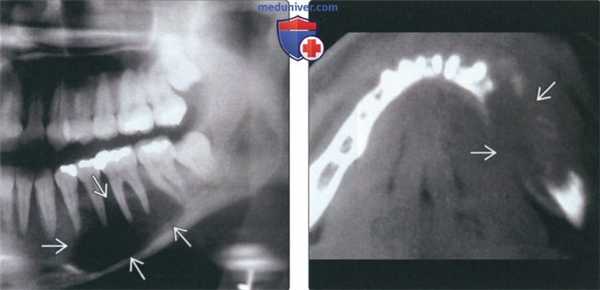

(Слева) На панорамной рентгенограмме определяется литическая остеосаркома нижней челюсти слева. Опухоль хорошо отграничена, рентгенонегативна, напоминает крупную кисту. Тем не менее, определяется расширение пространств периодонтальной связки вокруг зубов, позволяющее заподозрить злокачественную опухоль.

(Справа) На аксиальной КТ в костном окне у этого же пациента определяется деструкция кортикальных пластинок нижней челюсти. Сравните четкие края на панорамном изображении с плохо очерченными контурами, обнаруживаемыми на КТ.в) Дифференциальная диагностика остеосаркомы челюсти: